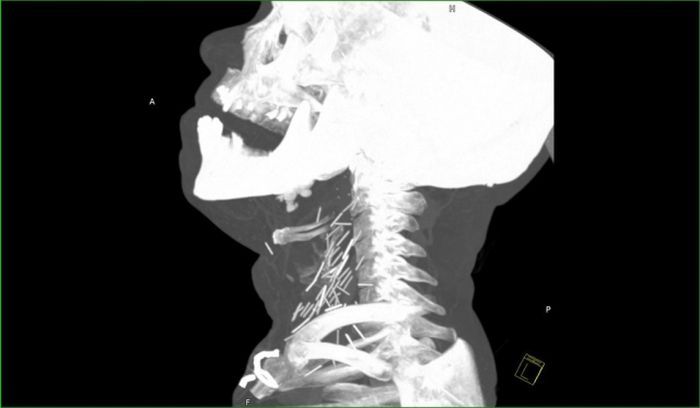

Рентген показал, что у чувака в шее огромное количество иголок.

Оказалось, что товарищ - нарк со стажем и все эти иглы остались в шее после неаккуратных инъекций.